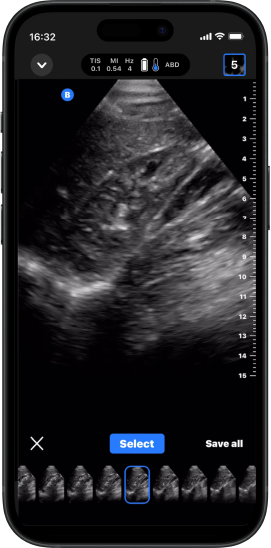

iQ Slice™

Em um momento em que a precisão é essencial, segure a sonda em um lugar enquanto ela captura várias imagens em um ângulo amplo.